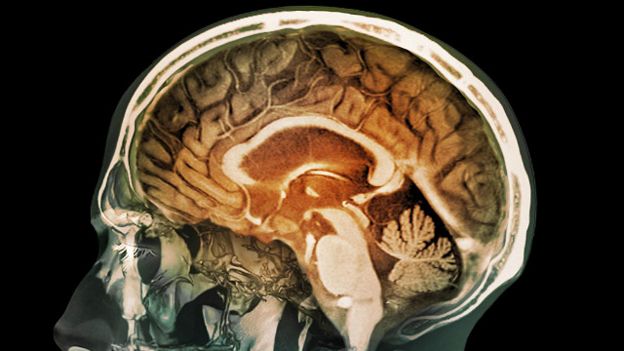

درد کی دوا کا تجربہ: 90 میں سے ایک شخص کا ’دماغ مردہ‘

فرانس میں درد کی ایک نئی دوا کے تجرباتی استعمال نے ایک شخص کے دماغ کو مردہ کردیا ہے تاہم دواساز کمپنی کا اصرار ہے کہ اس نے تمام بین الاقوامی ضابطوں کو مدِنظر رکھا تھا۔

رینیس کے ہسپتال میں موجود نیورولوجسٹ گائلز ایڈن کا کہنا ہے کہ اس دوا کا کوئی تریاق معلوم نہیں۔

ان کا کہنا ہے کہ ہسپتال میں زیرِ علاج پانچ میں سے تین مریضوں کے دماغ نے کام کرنا چھوڑ دیا ہے۔